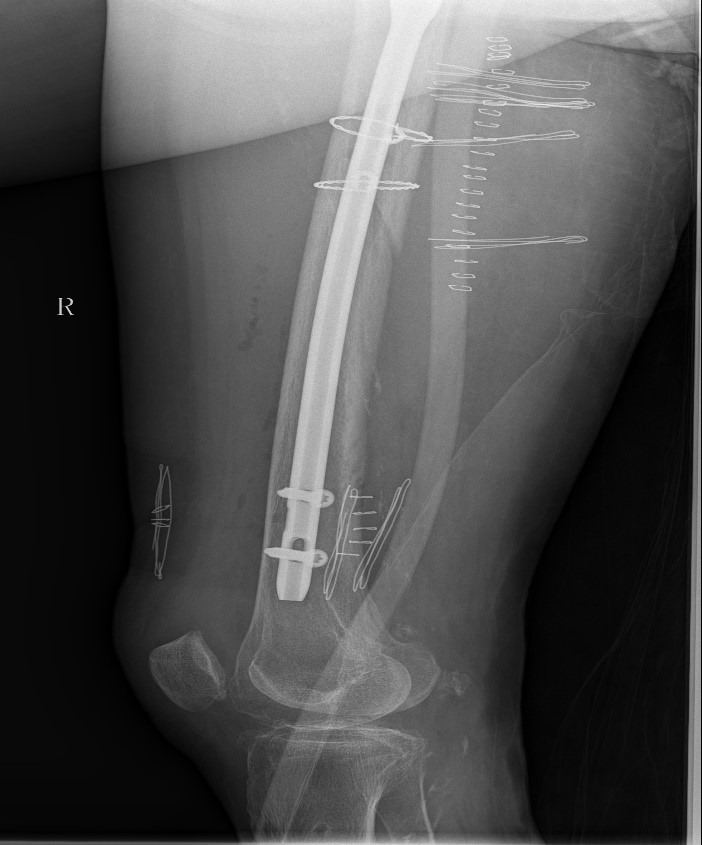

患者情况:熊奶奶,一个月前在金瓶梅电影因右髋骨折接受髓内针内固定术,术后康复中因不慎摔倒,再次出现右髋部疼痛并活动受限。经检查,确诊为股骨骨折。患者伴有帕金森病和高血压,身体状况较差。

患者情况:吴先生因路面湿滑不慎摔倒,导致右髋部疼痛并活动受限,经检查确诊为股骨粗隆间骨折。

1.骨折部位解剖重建的准确性;

2.内固定材料的选择及固定强度的保障。